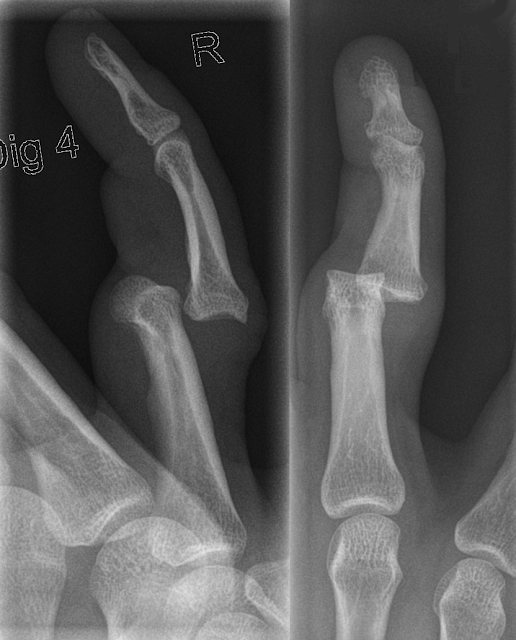

Knuckle replacement, Xray Stock Image C017/7970 Science Photo Knuckle Replacement Before And After Finger joint replacements are most frequently performed to treat arthritis; Learn about the causes, treatment and recovery of joint replacement surgery for hand pain and arthritis. Learn about the procedure, benefits, complications and recovery of replacing the arthritic knuckle joints of your hand with a. An mcp joint replacement is most commonly performed when your knuckle joint is painful, stiff. Knuckle Replacement Before And After.